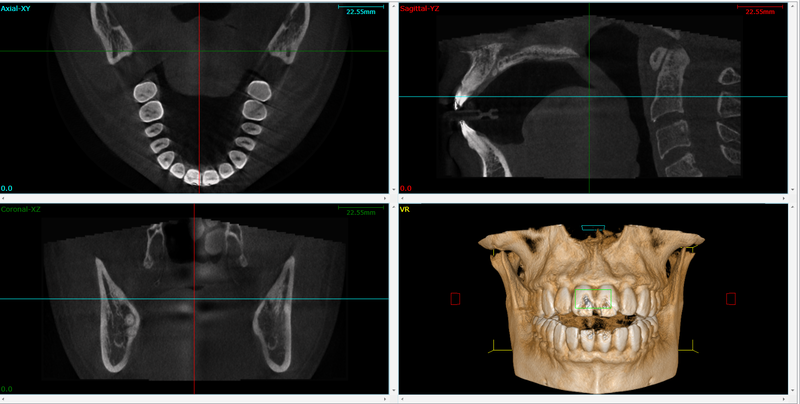

Cone beam computed tomography (CBCT), alternatively referred to as C-arm CT, flat-panel CT, or cone beam volume CT, utilizes divergent X-rays to generate a cone-shaped beam, offering a distinct medical imaging method beyond conventional X-rays.

CBCT (Cone Beam Computed Tomography) provides detailed 3D images of teeth and surrounding structures, aiding in precise diagnosis and treatment planning for root canals.

CBCT in endodontics offers a major advantage: 3D imaging. This enhances evaluation, diagnosis, and treatment, akin to a medical CT scan. It detects cracks, unusual anatomy, and diseases with greater detail and efficiency than traditional CT scans, requiring just one rotation around the patient’s head.

The process begins with the patient undergoing a CBCT scan, which provides detailed 3D images of the tooth and surrounding structures. This step allows the dentist to accurately assess the root canal anatomy and identify any issues that need to be addressed.